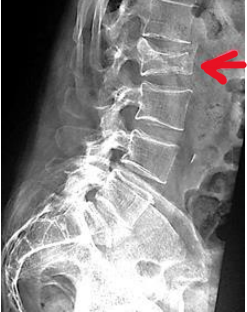

Observe a imagem e escolha a opção verdadeira sobre a

incidência.